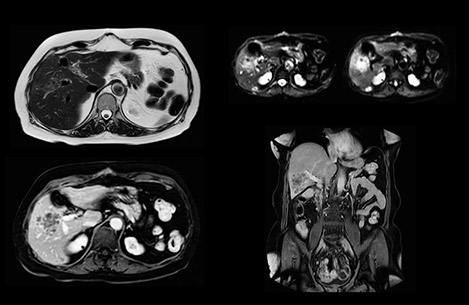

“Our liver exams are quite fast,” says Dr. Baumann. “If the patient tolerates it, we use an arms-up position to reduce the FOV and speed up the exam with dS SENSE.” “We acquire one transversal high resolution T2-weighted sequence with 3 mm slice thickness, for example for pancreas or liver lesions. Then we also add a T2 fat suppressed MultiVane XD SPIR sequence. We perform these two routinely in our liver imaging. We use high dS SENSE factors to significantly shorten scan times to 2-4 minutes, which can improve our protocol; it’s a very robust scan.” “We include mDIXON for the dynamic sequences because of the robust and homogeneous fat suppression we get with that. We had been using eTHRIVE, but we are now quite happy with mDIXON. Sometimes we use a medication to calm the bowels, to further improve the image quality.”